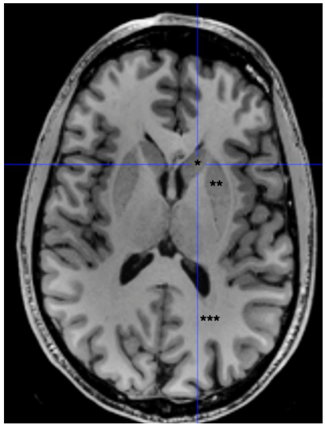

Observe a imagem a seguir.

As três áreas com asteriscos correspondem, respectivamente, às seguintes estruturas: